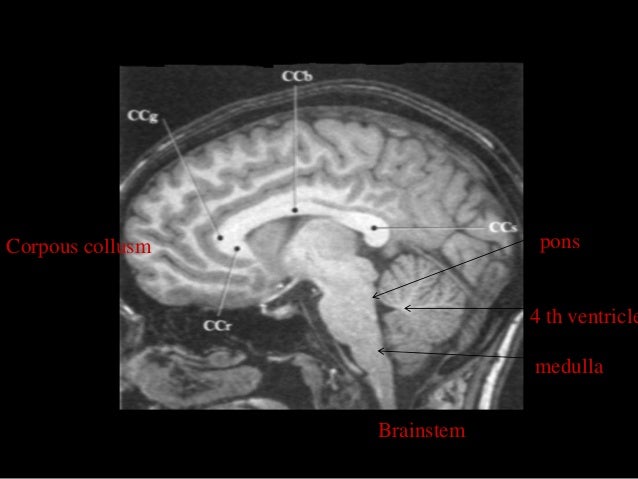

MRI SECTIONAL ANATOMY OF BRAIN diagram scalp above